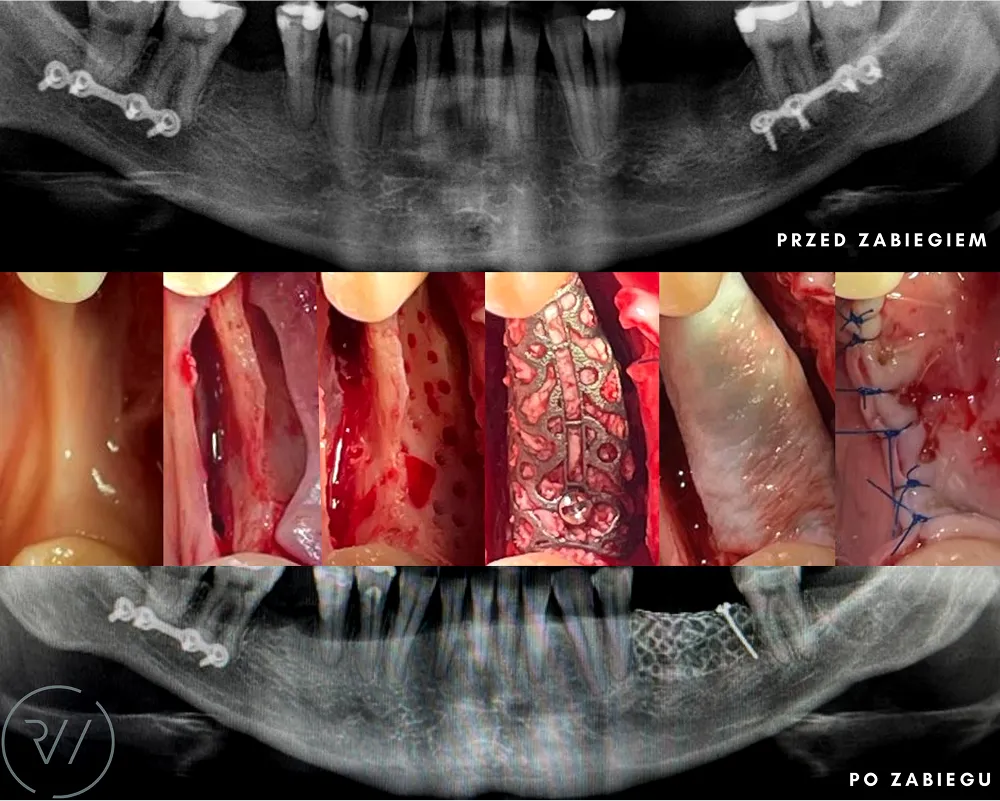

TRÓJWYMIAROWA REKONSTRUKCJA WYROSTKA ZĘBODOŁOWEGO PRZY UŻYCIU INDYWIDUALNIE DRUKOWANYCH SIATEK TYTANOWYCH YXOSS ReOss

To kolejna metoda umożliwiająca precyzyjną odbudowę zadanego kształtu tkanki kostnej przy użyciu standardowych materiałów kościotwórczych, kości własnej lub PRF oraz zewnętrznego rusztowania w postaci siatki z biozgodnego stopu tytanu. Siatka jest indywidualnie projektowana w technologii CAD CAM i następnie drukowana dla konkretnego przypadku.

Dotychczas stosowane stabilizatory zewnętrzne w formie siatek tytanowych używane do regeneracji kostnej lub w zabiegach odtwórczych w chirurgii szczękowo-twarzowej uwzględniały materiały ręcznie doginane i formowane podczas zabiegu operacyjnego. Zastosowanie technologii CAD CAM dla potrzeb druku materiałów przeznaczonych do indywidualnej rekonstrukcji kostnej znacznie poprawiło precyzję i jakość uzyskiwanych efektów. Wdrożenie biozgodnych stopów tytanu do druku siatek zdecydowanie ograniczyło odsetek powikłań zapalnych.

Precyzja projektu druku siatki bazuje na dokładności odwzorowania kształtu kości w stożkowej tomografii komputerowej CBCT, co zapewnia ich dobre przyleganie do podłoża kostnego oraz ogranicza powstawanie powikłań w postaci obnażania się siatek. Precyzja projektu oraz materiał, z którego wykonana jest siatka (biozgodny stop tytanu), powodują, że obnażenie się siatki nie zaburza procesu gojenia i regeneracji kostnej.

Wymaga jedynie większej ilości kontroli pozabiegowych oraz wzmaga czujność higieniczną zarówno ze strony lekarza, jak i pacjenta. Ten rodzaj odbudowy kostnej stosowany jest w sytuacjach złożonych, trójwymiarowych 3D ubytków kości, przy których standardowe metody odbudowy są niewystarczające. Ilość kości, którą możemy uzyskać, stosując tę metodę, to nawet kilka centymetrów sześciennych.

Metoda rekonstrukcji kostnej w oparciu o indywidualnie drukowane siatki z tytanu dla implantacji wszczepów śródkostnych stosowana jest najczęściej jako dwuetapowa. W pierwszym etapie odbudowywana jest kość, natomiast implanty wszczepiane są po okresie 4–6 miesięcy. Na wgojenie implantów oczekujemy od 4 do 6 miesięcy w zależności od miejsca ich lokalizacji. Siatka tytanowa po spełnieniu swojej funkcji rusztowania dla odbudowującej się kości jest następnie usuwana w dniu wszczepienia implantu. Jeżeli kość spełnia odpowiednie warunki, istnieje możliwość zastosowania modyfikacji siatki tytanowej, która umożliwia jednoczesne wprowadzenie implantów wraz z odbudową kostną.

Wariant ten skraca czas od pierwszego zabiegu do wykonania gotowych koron protetycznych na wprowadzonych implantach. Opisane schematy procedur regeneracyjnych wykazują znaczną innowacyjność, jeśli chodzi o wykorzystanie technologii cyfrowej w medycynie odtwórczej. Natomiast w codziennej praktyce chirurgicznej poprawiają precyzję, tempo oraz przewidywalność w świadczeniu usług polegających na odbudowie zniszczonych lub zdeformowanych ludzkich tkanek.